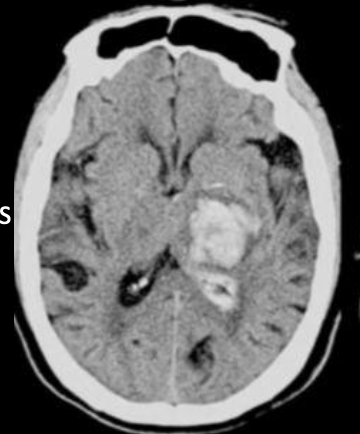

17

Q

A

EVC hemorragico

hipertensivo